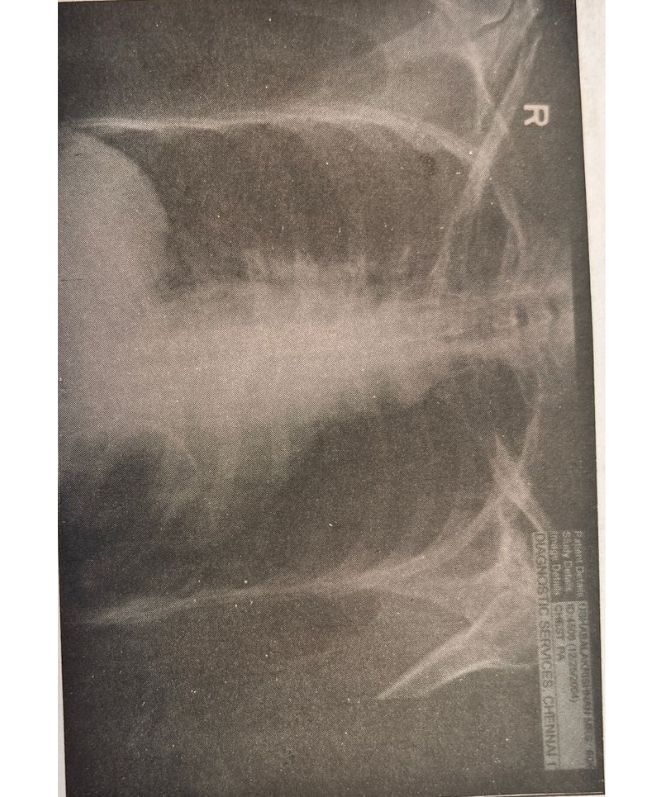

- Lung Cancer Scans – 2

Lung Cancer Scans 2

1

2

3